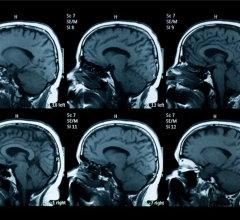

June 11, 2024 — A new ultra-high-performance brain PET system allows for the direct measurement of brain nuclei as never ...

June 3, 2024 — MRI scans are commonly used to diagnose a variety of conditions, anything from liver disease to brain ...